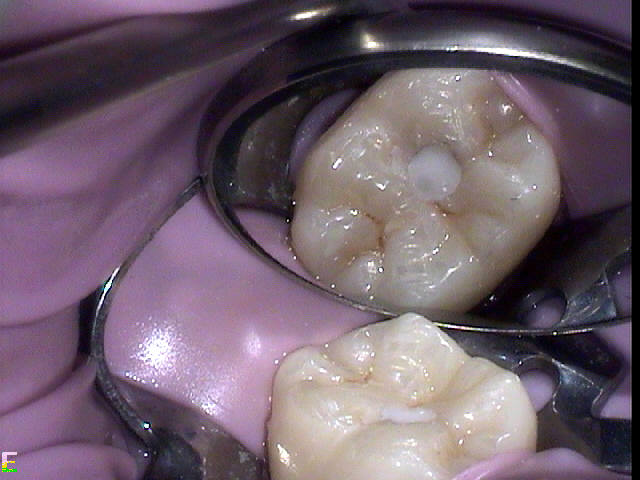

Figure 4 through Figure 10 depict several teeth that have conservative accesses while still allowing the clinician to adequately instrument and clean each tooth to achieve effective root canal therapy. The success of these cases still hinges on the proper cleaning and shaping of the root canal system, and while conservative accesses are desirable, too small of an access can lead to missed canals, poor instrumentation, improper cleaning, and, ultimately, a failed procedure.

Fig 6. Tiny access specifically performed to preserve tooth structure and avoid the rest seat of a maxillary partial denture.

Figure 6